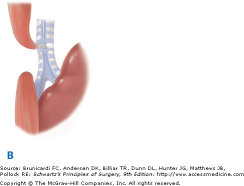

25. Esophageal Atresia and Tracheoesophageal TES:- The most commonly seen variety is EA with distal TEF (type C), which occurs in approximately 85% of the cases in most series. The next most frequent is pure EA (type A), occurring in 8 to 10% of patients, followed by TEF without EA (type E). The latter occurs in 8% of cases and is also referred to as an H-type fistula, based on the anatomic similarity to that letter (Fig. 39-9). EA with fistula between both the proximal and distal ends of the esophagus and trachea (type D) is seen in approximately 2% of cases, and type B, EA with TEF between the proximal esophagus and trachea, is seen in approximately 1% of cases.

The five varieties of esophageal atresia (EA) and tracheoesophageal fistula (TEF). A. Isolated EA.(SECOND MOST COMMON) B. EA with TEF between the proximal segment of the esophagus and the trachea. C. EA with TEF between the distal esophagus and the trachea(MOST COMMMON) D. EA with fistula between both the proximal and distal ends of the esophagus and the trachea. E. TEF without EA (H-type fistula).(THIRD MOST COMMON)